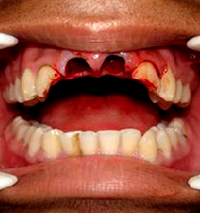

A 14 year old boy with reimplantation of avulsed maxillary central incisors

A 14 year old boy, came to the Department with the complaint of accidental missing of upper two central incisor teeth (Figure 1A, B). The teeth were brought by the patient those were healthy and intact. His medical history was non-contributory and he was tetanus immunized. He came 2 hours after the accident with the missing teeth immersed into 0.9% sodium chloride solution. On clinical examination, there were missing of both central incisors. Sockets were full of blood. On palpation, no other tooth was tender.